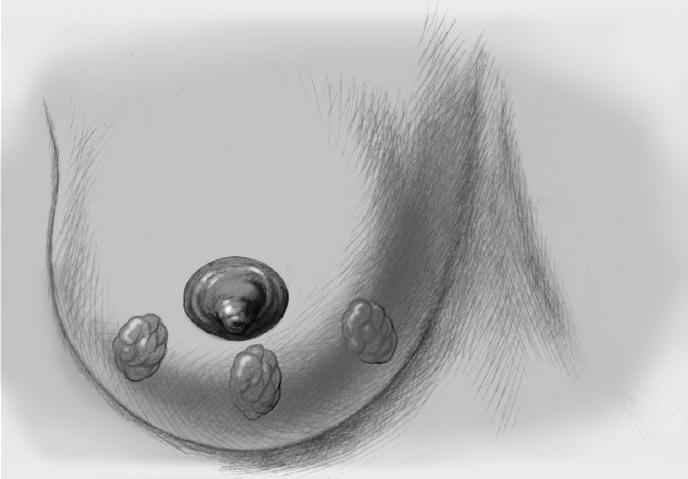

The former tumor region is marked with titanium clips (usually three clips for spatial orientation).

The former tumor region is marked with clips.

The former tumor bed is marked with clips for optimized postoperative radiotherapy.

The tumor bed is marked with clips for accurate radiotherapy planning.